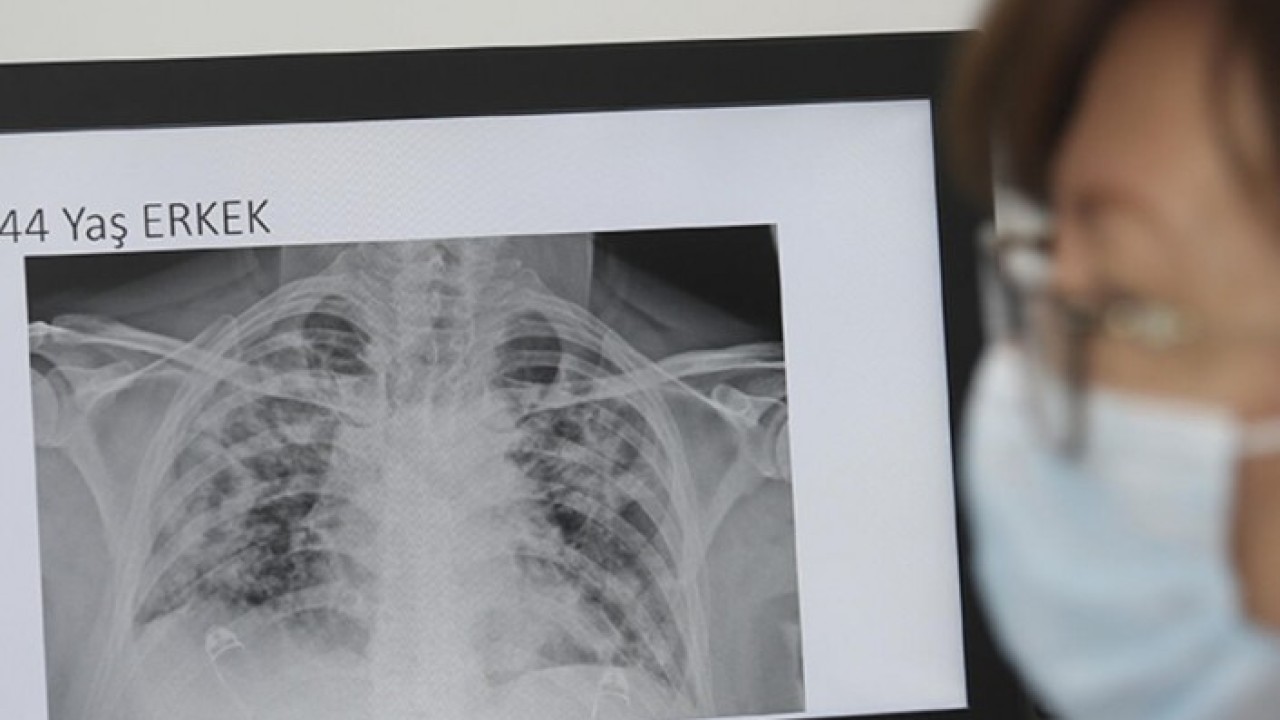

Sözcü'nün haberine göre, bilim insanının paylaştığı röntgen sonuçları dikkat çekti. Soldaki görselde sigara içen bir bireyin akciğer filmi görülürken sağda ise koronavirüsü yenmiş bir bireyinki yer alıyor. Akciğer filminde siyahlar ne kadar fazlaysa o kişinin ciğer kapasitesi ve sağlığı o kadar iyi anlamına gelir. Beyazlığın artması akciğerin kapasitesinin azaldığı anlamına gelir.

Röntgen sonuçlarında koronavirüsü geçirmiş ve sağlığına kavuşmuş kişilerin ciğerlerindeki hasarın sigara tiryakilerinden çok ama çok daha kötü olduğunu gösteren Bankhead-Kendall, “Sağlıklı bir bireyin röntgen sonucunda siyah alan büyük olur. Bu da o kişinin ciğerlerine alabileceği oksijen seviyesini gösterir. Sigara içenlerde hafif hareler yer alırken Covid-19 hastalarının ciğerleri ise bembeyazdır. Yani bu da koronavirüsü yenenlerde bile akciğer sorunları yaşanabildiğini gösteriyor” dedi.

Bankhead-Kendall, kıyaslama yapmak için sağlıklı bir bireyin akciğer filmini de paylaştı.